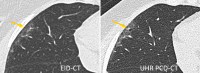

Novel photon-counting detector CT (PCD-CT) has the potential to address the limitations of previous CT systems, such as insufficient spatial resolution, limited accuracy in detecting small low-contrast structures, or missing routine availability of spectral information. In this review article, we explain the basic principles and potential clinical benefits of PCD-CT, with a focus on recent literature that has grown rapidly since the commercial introduction of a clinically approved PCD-CT.